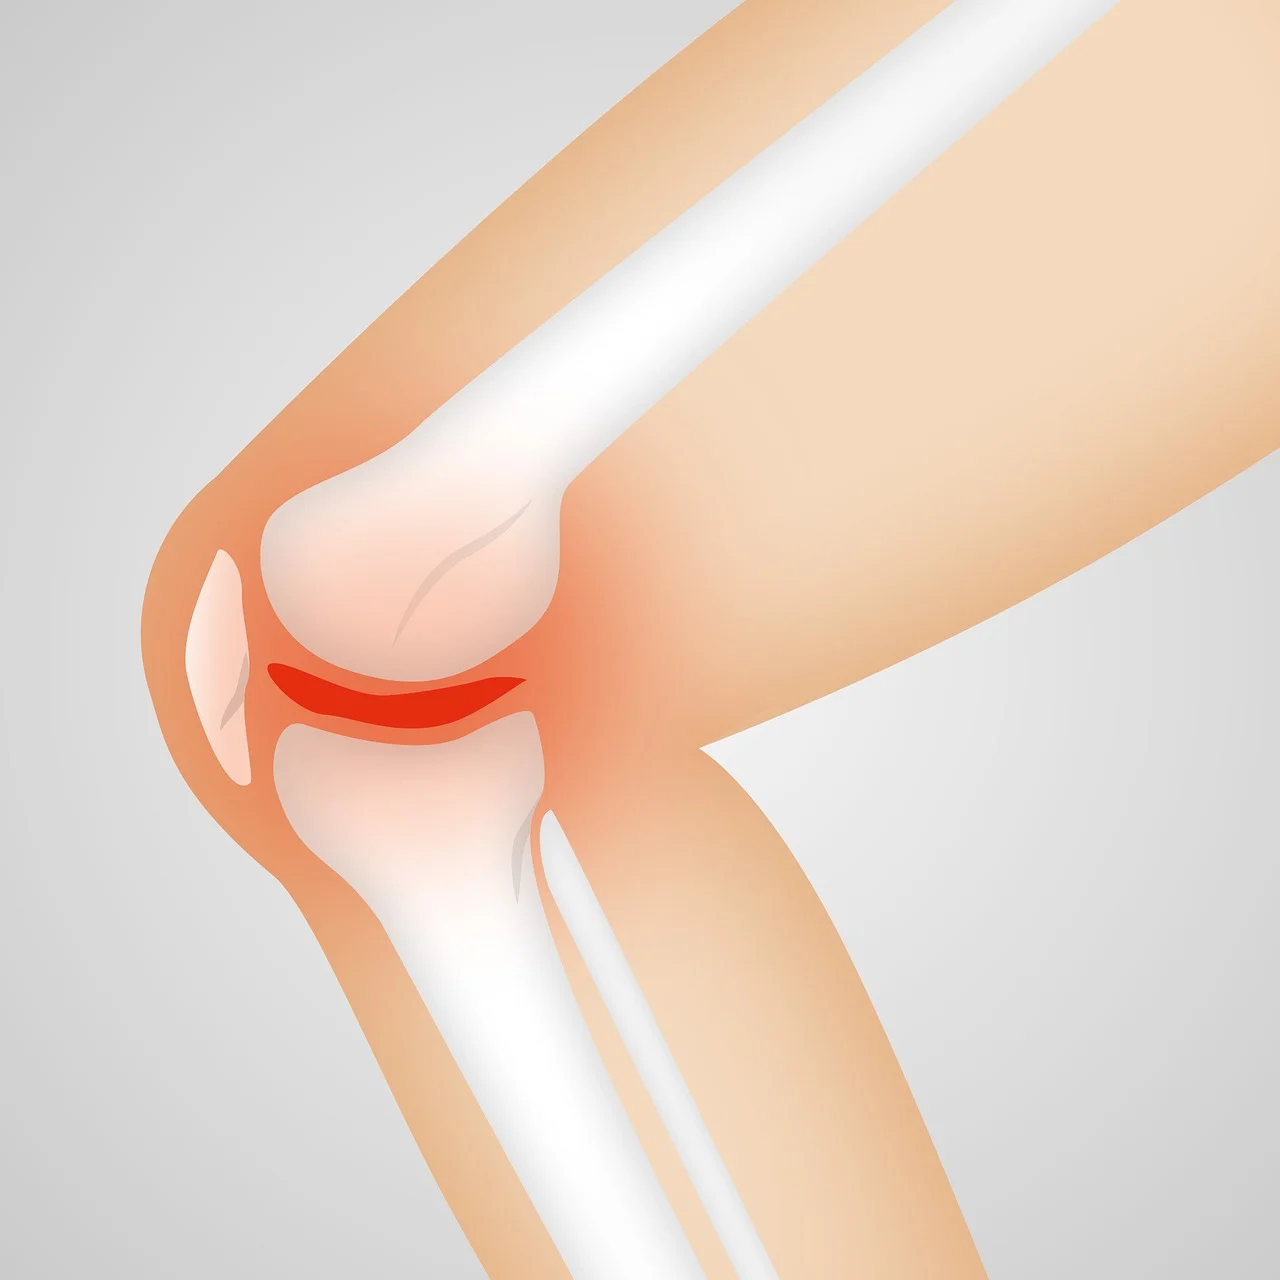

무릎에 물이 차는 증상은 운동선수가 꼭 아니더라도 무릎이 갑자기 붓고 통증이 오는 것 부터 시작합니다. 나이가 들면 노화로 인해서도 이런 경우가 있을 수 있습니다. 외상일 수도 있고 무릎 주위로 부어오르는 느낌을 받는경우 무릎 삼출액이라고 하는 무릎에 물이 차는 증상이 발생합니다.

운동선수들도 위와같이 밴드 등을 착용하는 경우가 많습니다. 연골이 손상하고 무릎에 활액이 분비되면서 물이 차는 증상이 발생하게 되는 것 인데요, 골절일수도 있고 관절염일 수도 있으며 패혈성 관절염이나 연조직염 같은 감염에 의한 원인이 있을 수도 있습니다.

퇴행성 관절염은 말 그대로 노화로 인해 생기는 병으로 뼈의 관절면을 감싸고 있는 관절의 연골이 마모되어 생기는 병입니다. 관절 주변에 활액막에 염증이 생기고 이 염증이 치료되지않을 경우 통증이 심해지면서 물이 차기도 합니다.